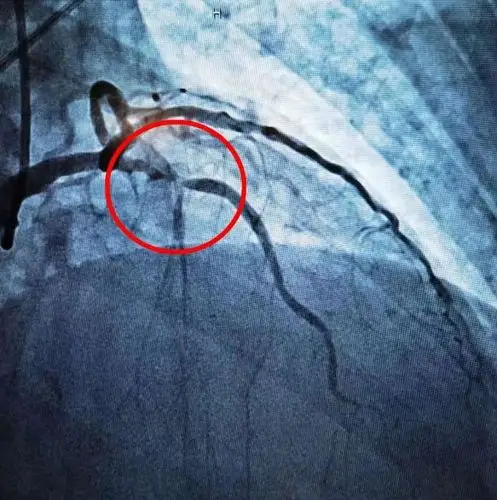

右冠脉两处重度狭窄,近端那个狭窄太严重了,说堵死就堵死了,一旦堵上

楼朝臣副主任为胡大伯行急诊经皮冠脉造影术.

冠状动脉狭窄